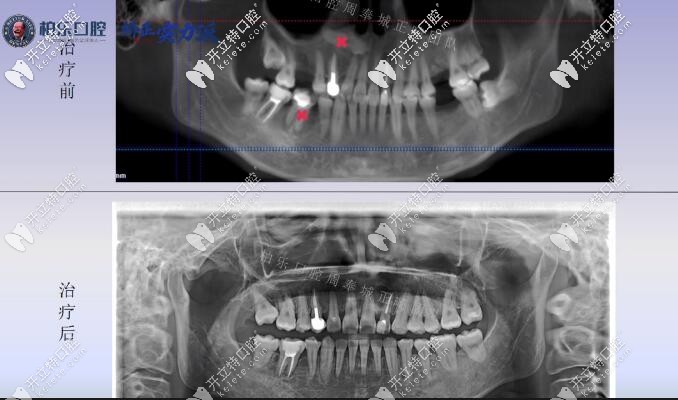

后牙缺失三顆大牙的x線片

癥狀:上牙左右各缺失了一顆大磨牙,下牙左側(cè)缺失一顆大牙;并且從X線片看,上頜唇側(cè)的前牙位置上有一顆多生牙是需要拔除的,還有一顆阻生智齒。顧客也沒(méi)想到自己30歲了還能長(zhǎng)智齒。

看看整個(gè)案例矯正前后的X線片對(duì)比,竟然連智齒也扶正了。

南寧柏樂(lè)口腔缺失三顆矯正案例X線片前后對(duì)比

紅叉的地方就是多生牙的位置和沒(méi)有保留價(jià)值的大牙。

從矯正x線片對(duì)比基本可以看出來(lái)其實(shí)難度較大的是智齒豎直,現(xiàn)在治療已經(jīng)結(jié)束,從智齒的位置可以看出來(lái):基本已經(jīng)扶正是可以使用的功能牙。